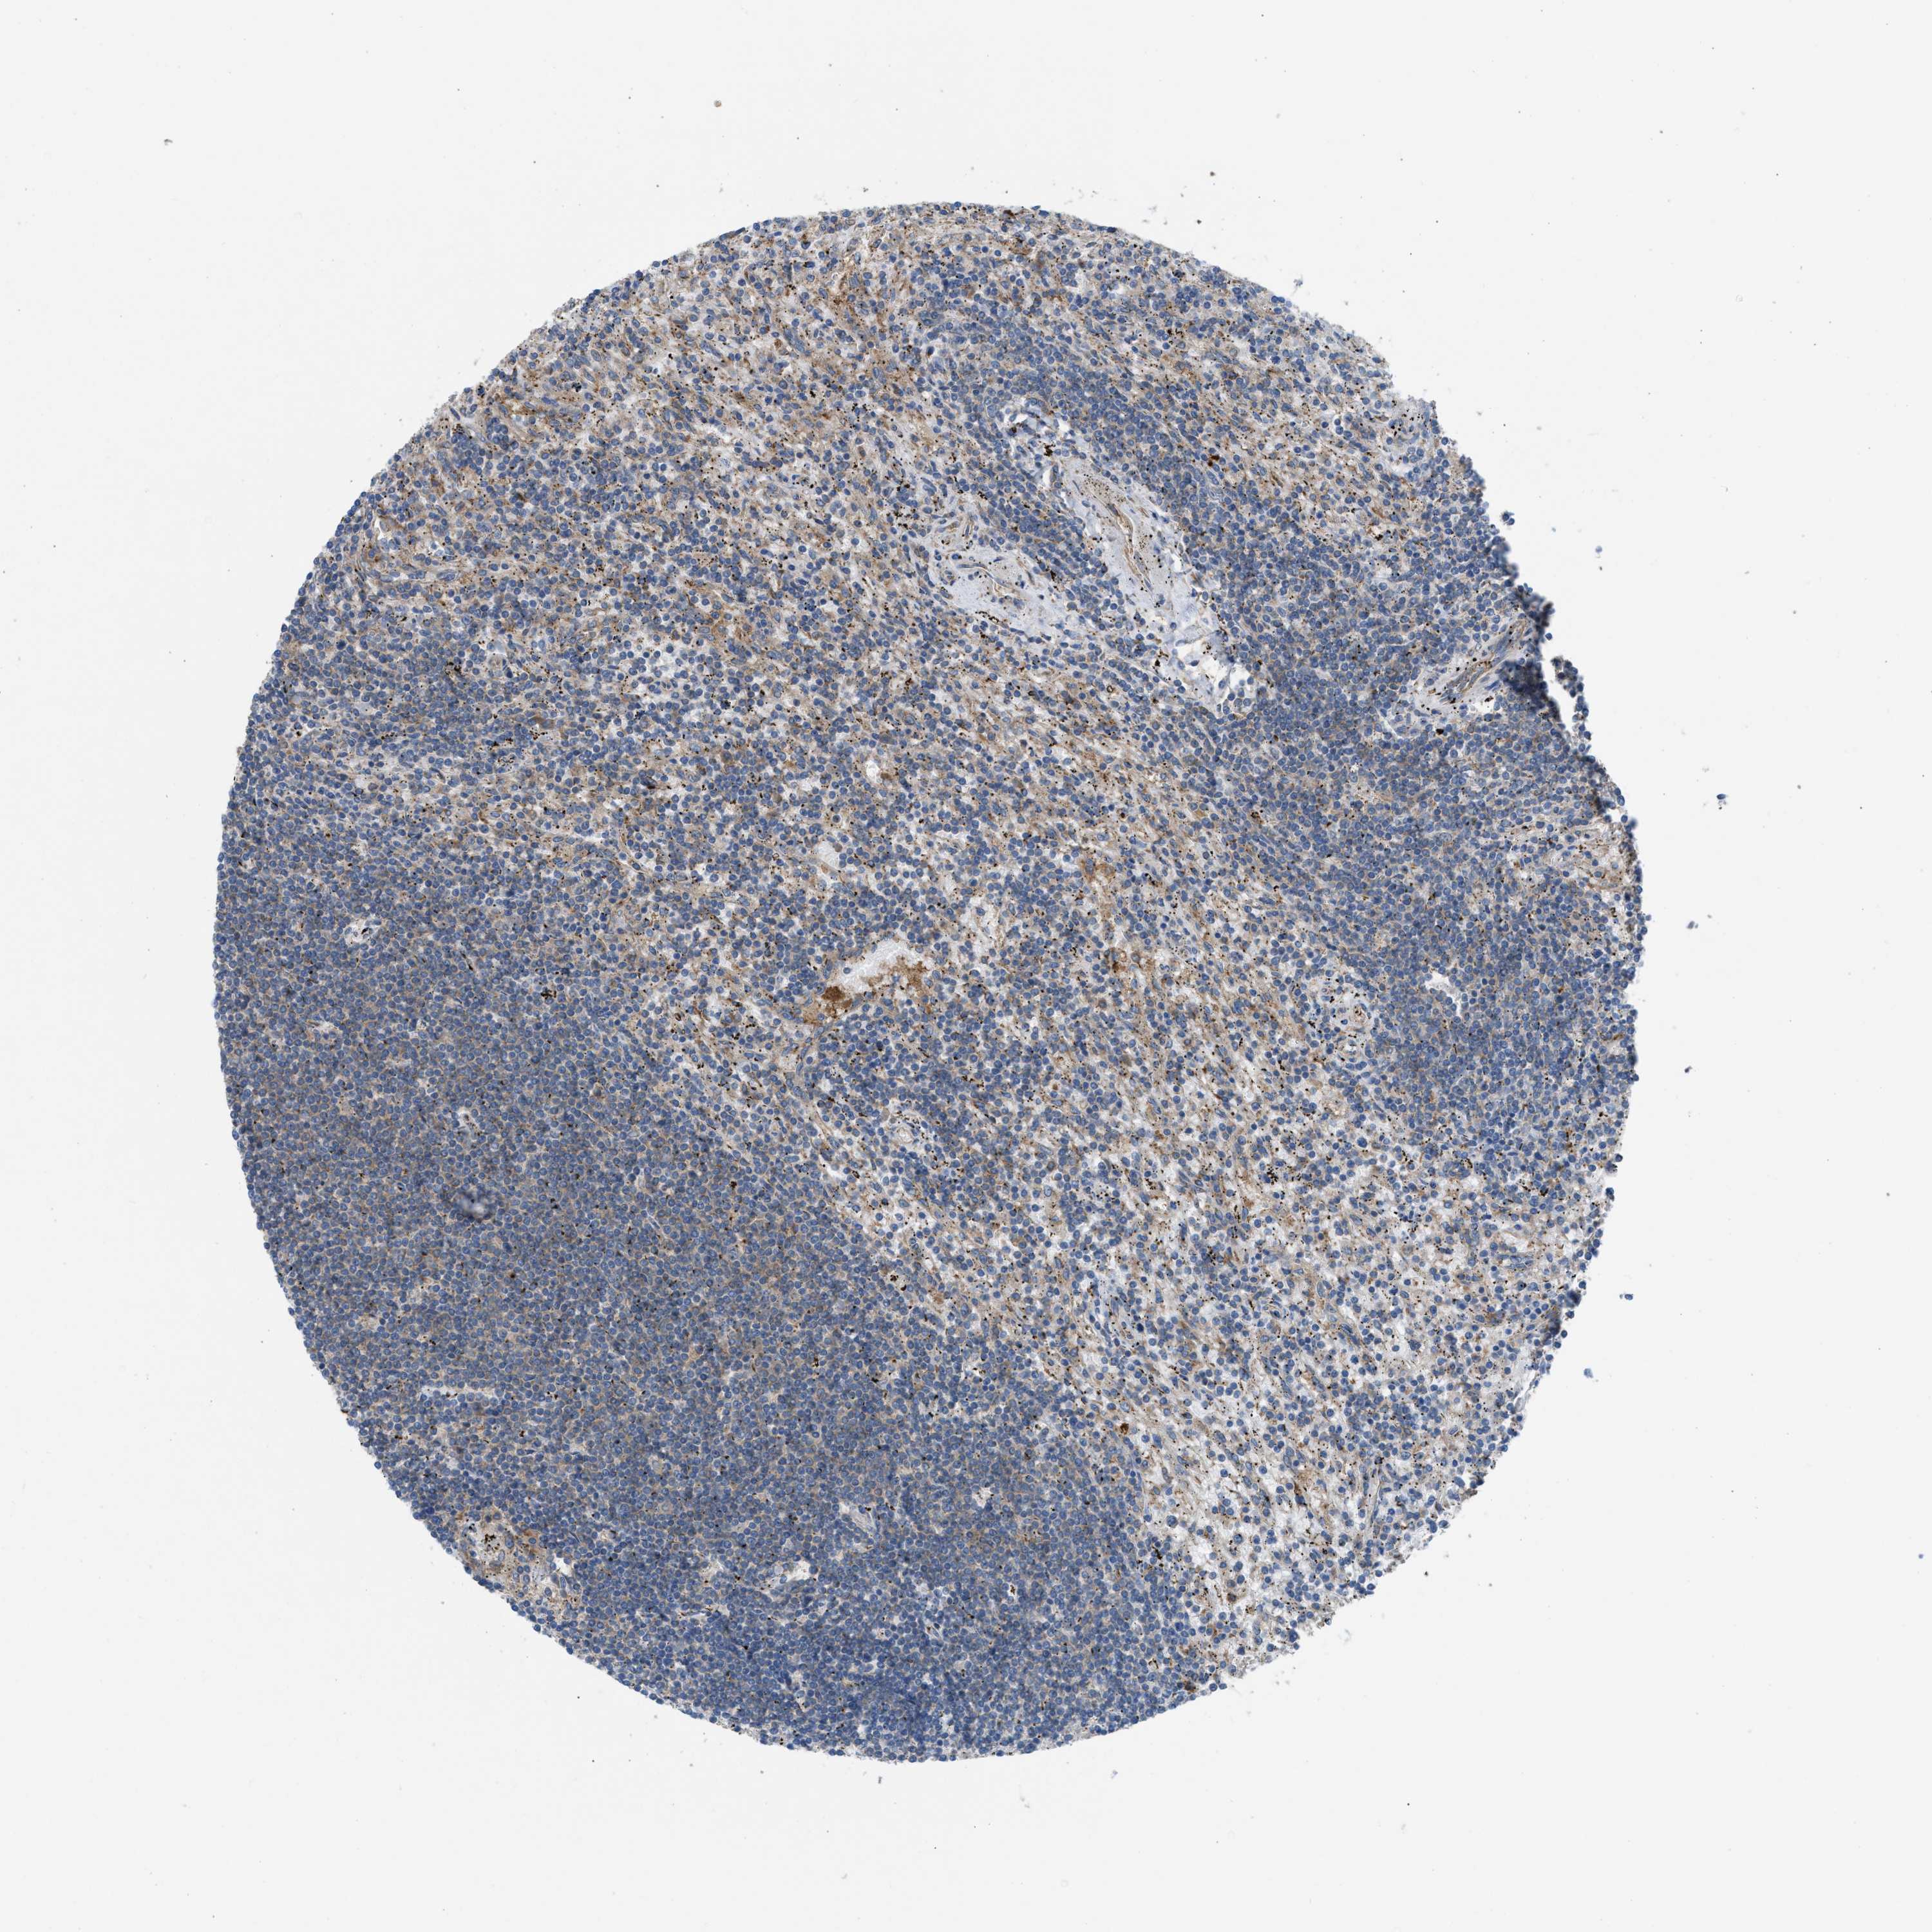

LYMPHOMA - Protein expressioni

A mouse-over function shows sample information and annotation data. Click on an image to view it in a full screen mode. Samples can be filtered based on level of antibody staining by selecting one or several of the following categories: high, medium, low and not detected. The assay and annotation is described here.

Antibody staining in the annotated cell types in the current human tissue is reported as not detected, low, medium, or high, based on conventional immunohistochemistry profiling in selected tissues. This score is based on the combination of the staining intensity and fraction of stained cells.

Each image is clickable and will lead to virtual microscopy that enables deeper exploration of all samples and also displays staining intensity scores, fraction scores and subcellular localization as well as patient and tissue information for each sample.

Antibody HPA021197

Malignant lymphoma, non-Hodgkin's type, Low grade